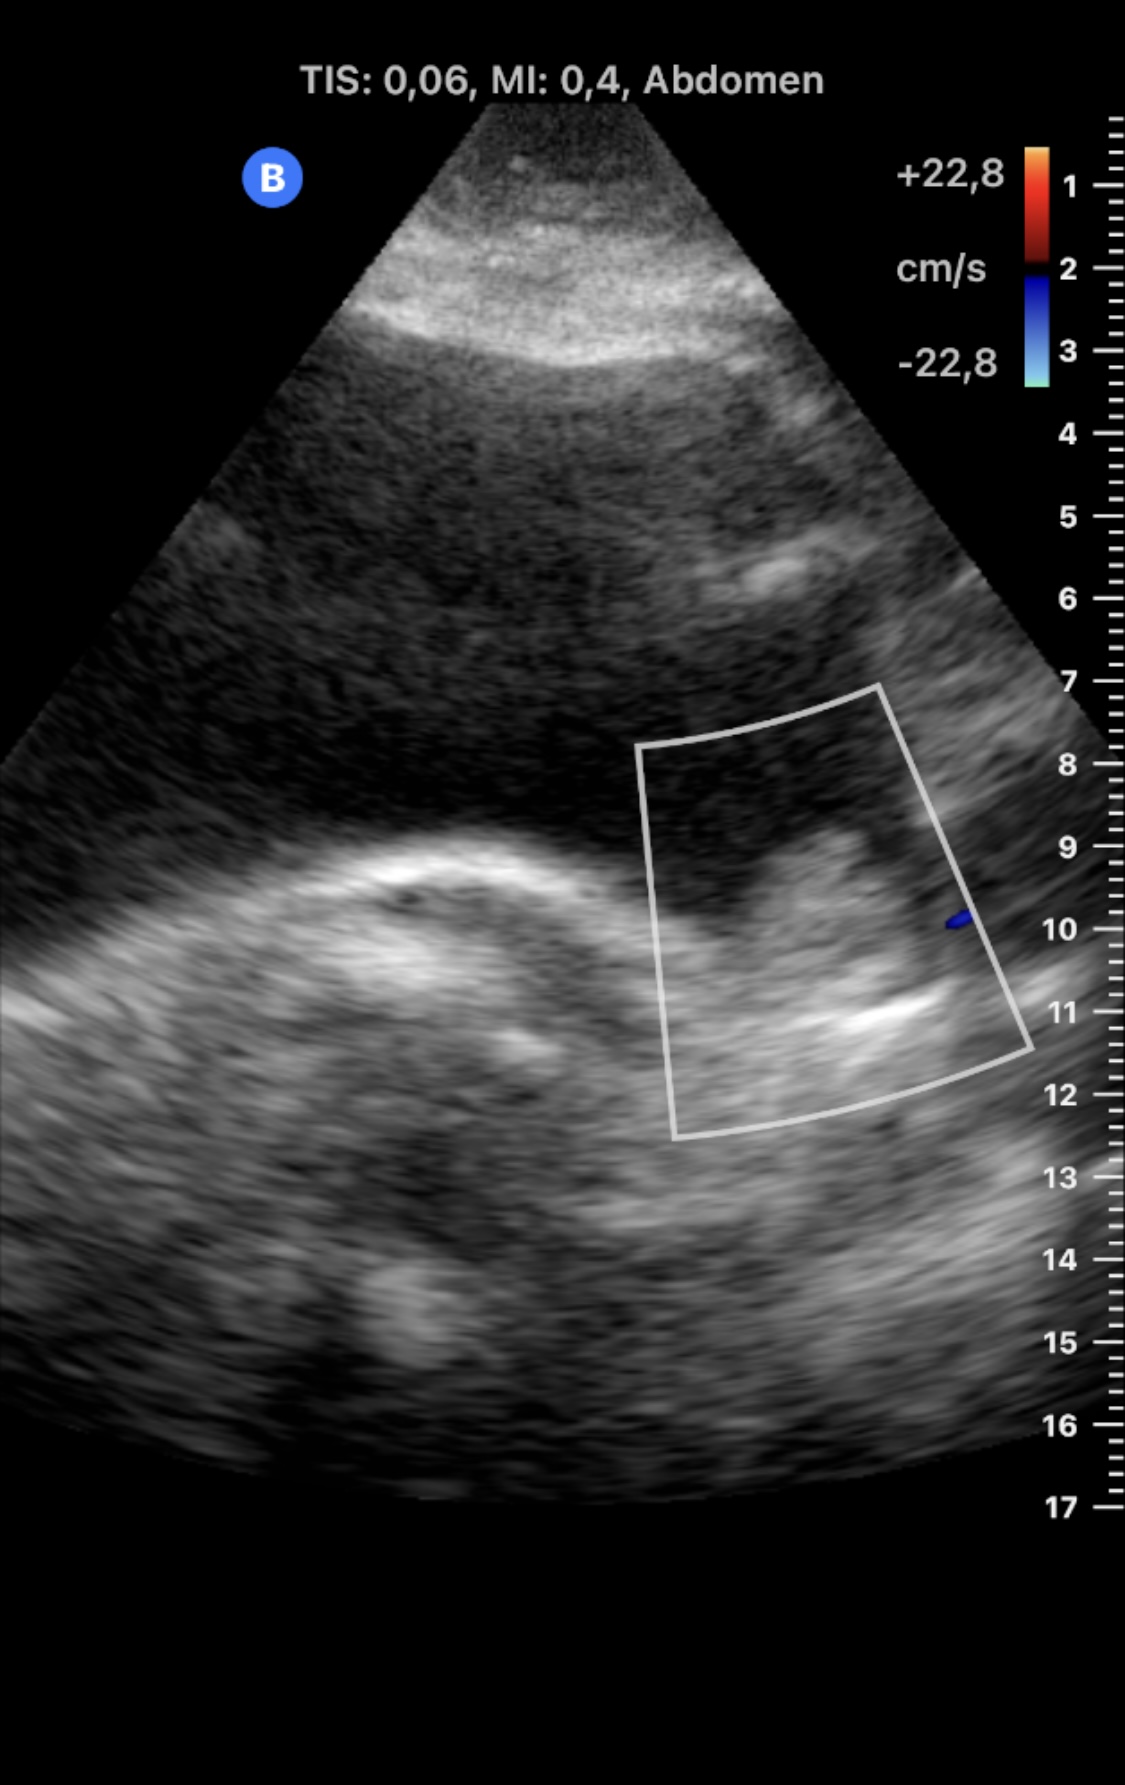

Realizamos Ecografía clínica en consultorio rural, con sonda portátil: riñones con ecoestructura, tamaño y localización normales. Ausencia de dilatación de vías urinarias. Vejiga bien repleccionada en la que se objserva en la base izquierda de la vejiga una imagen homogénea, sólida, intravesica y dependiente de la mucosa, sin sombra acústica posterior. No se modifica con el cambio postural de la paciente.

En urgencias se realizó ecografía reglada: «...Vejiga poco replecionada, poco valorable en este estado, observándose en su margen inferior izquierdo, lo que parece corresponder con una lesión de partes blandas de unos 27,5 x 14 x 26,2 mm y márgenes lobulados, que no se modifica con los cambios posturales».